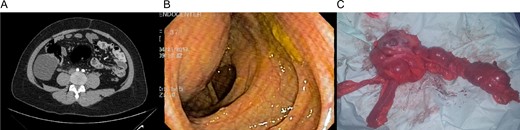

Patient is a 36-year-old woman without any past medical history, she was complaining of lower abdominal pain for about a month. Clinical examination revealed a palpable mass in the lower abdomen. A contrast-enhanced abdominal computed tomography (CT) revealed an 8 × 8 × 6 cm3 cystic lobulated mass dependent of the cecum wall, without any lymph nodes of hepatic masses (Fig. 1A). Complete blood count and laboratory exams were normal. Colonoscopy demonstrated an extrinsic compression of the lateral wall of the ascending colon. However, the mucosa and the rest of the colon appeared normal (Fig. 1B).

(A) CT revealing a 7 × 8 cm2 cystic lobulated mass dependent of the cecum wall. (B) Colonoscopy showing extrinsic compression of the lateral wall of the ascending colon. (C) Colonic mass and right colon.